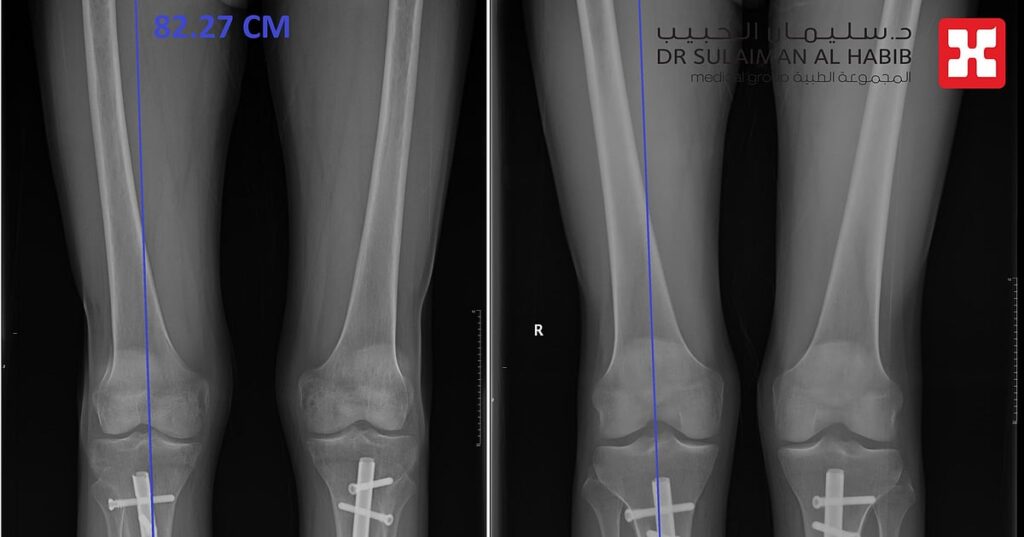

يواصل مستشفى الدكتور سليمان الحبيب بالخبر، تميزه اللافت في إجراء عمليات تطويل العظام، عبر تقنية المسمار النخاعي الممغنط، والتي تعتبر من أكثر تقنيات تطويل العظام فعالية، وتتسم بأنها تتم دون آلام أومثبتات خارجية تقيد حركة المراجع، وأنهت هذه العمليات معاناة العديد من الحالات من تباين في طول الأطراف السفلية، أوتشوهات القدمين، وكما أنها حققت آمال الأشخاص الراغبين في زيادة طولهم لأهداف متصلة بالتجميل وتحسين المظهر.